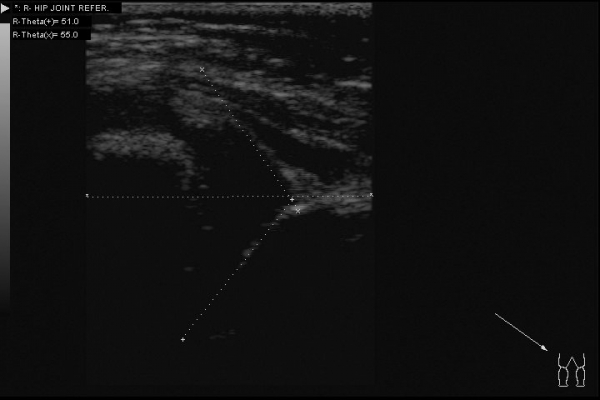

Доброго всем дня. Интересный случай сегодня: клинически у ребенка (2,5 месяца) все нормально -- отведение в полном объеме, ротация -- норма. Складки -- симметрия. Но!!! В анамнезе у мамы ребенка врожденный вывих бедра. Решил выполнить УЗИ:

Таким образом видим полное соответствие УЗИ картины -- рентгенограмме.